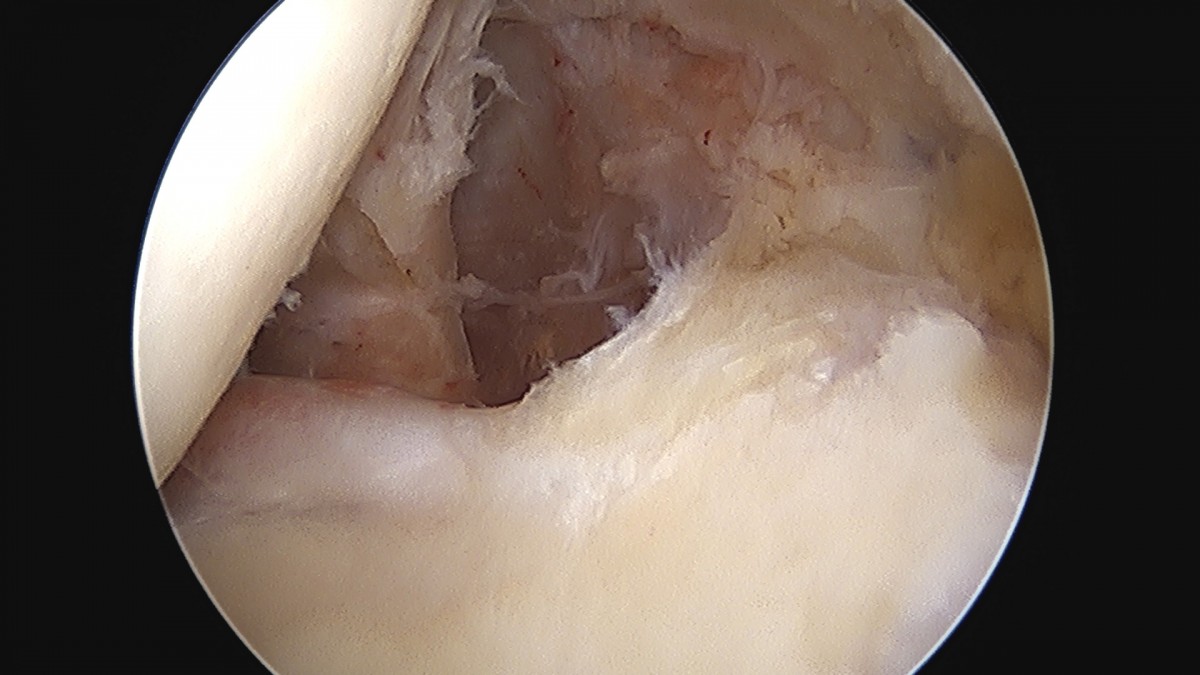

이재상원장님 어깨 이두박건 절제술 정하O 환자

dae765e4d9ac96aee867c9d6292d8784_1758006941_607.jpg